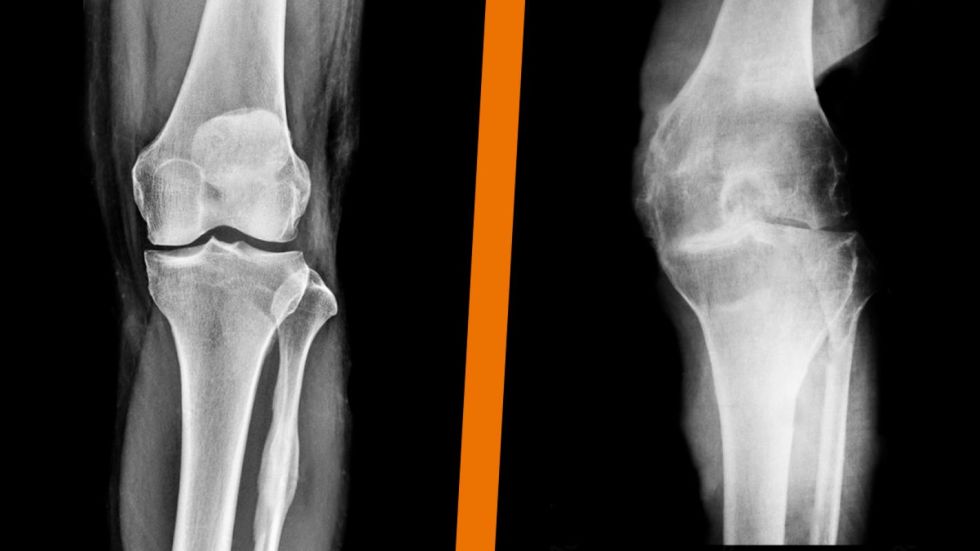

Es una enfermedad articular predominantemente degenerativa y con leve inflamación que afecta al cartílago, hueso y tejidos blandos. Forma parte de las enfermedades reumáticas. Produce dolor y afecta directamente la movilidad y autonomía de la persona, llevando también a un desgaste psicológico, donde la tarea más habitual puede convertirse en un gran obstáculo que afrontar debido a las limitaciones asociadas a la patología.

¿CÓMO SE DIAGNOSTICA?

Todo paciente que presente los síntomas anteriormente mencionados debe consultar con un reumatólogo, quien después de examinarlo hace el diagnóstico clínico e imagenológico, para de esta manera poder controlar la progresión de la enfermedad y evitar futuras discapacidades.